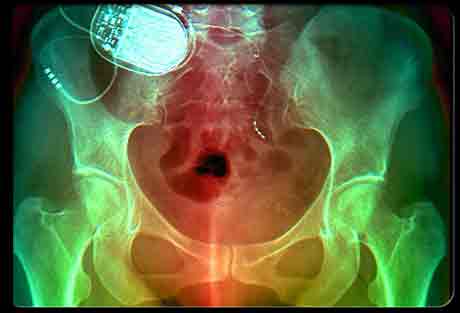

Хирургическое лечение стрессового недержания может быть амбулаторной процедурой. Что касается неотложного недержания мочи, то в этом случае врач имплантирует устройство, которое стимулирует нервы, расположенные рядом с мочевым пузырём, и контролирует спазмы мышц с помощью электрических сигналов (показано на рисунке). При стрессовом недержании хирург может поместить мочевой пузырь в так называемый слинг (sling, подпорка под мочевым пузырём)) – кусок ткани или иного материала, который удерживает пузырь в верхнем положении и предотвращает утечки. При другом варианте операции мочевой пузырь подтягивается в верхнее (нормальное) положение без использования слинга.